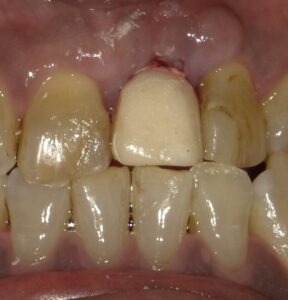

差し歯を外すと十分な根の長さがないのがわかります。抜歯を行いました。